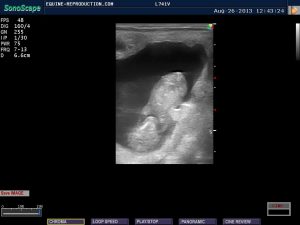

The allantoic sac has now enlarged and elevated the embryo dorsally (upwards) while the yolk sac has almost completely regressed. By around 36 days, the embryonic ascent will be complete, and the umbilical cord will be forming at the dorsal pole. Blood flow within the embryo is clearly visible in the color doppler image. Around this time, the endometrial cups will have formed in the region of the chorionic girdle which forms where the allantoic and yolk sacs meet. The endometrial cups are responsible for the secretion of the hormone equine chorionic gonadotropin (eCG) which in turn is responsible for promotion of the production of secondary CLs which will increase progesterone to assist pregnancy maintenance until around 100 days of pregnancy. At 40 days the term for the developing foal will change from “embryo” to “fetus” in recognition in part of the changed state of nutritional source as the umbilicus is formed, and the allantochorion commences attachment to the endometrium, becoming the placenta – a process which is not completed until around 140 days of pregnancy. In the near future the size of the fetus will preclude its being entirely visible in mare ultrasound pregnancy images.

The internal bloodflow of the fetus is now clearly visible, as well as some umbilical flow. The small remnant of the yolk sac can be seen still attached to the left.

The internal blood-flow of the fetus is clearly visible, as well as umbilical flow. The small remnant of the yolk sac can be seen still attached to the left.

This side view of the fetus clearly shows the head at the top, with limbs being visible.